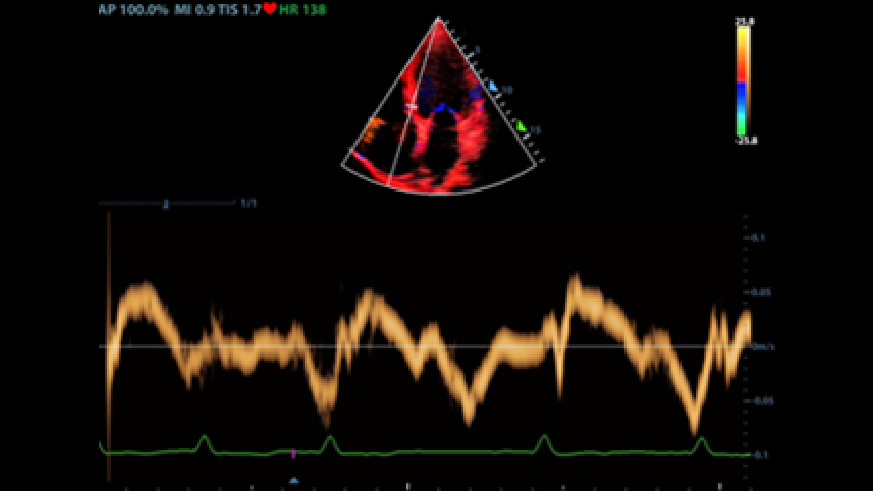

Des outils intelligents pour la gestion des fluides

2Smart VTI (ITV)

Mesure automatique de lâintÃĐgrale temps Vitesse (ITV) et du dÃĐbit cardiaque pour permettre une ÃĐvaluation rapide de la fonction cardiaque. Lâoutil place automatiquement la boite couleur et la ligne de tir du doppler pulsÃĐ en temps rÃĐel. Un graphique de tendances reprÃĐsentant le dÃĐbit cardiaque, le volume dâÃĐjection systolique et lâITV aide à la prise de dÃĐcision.